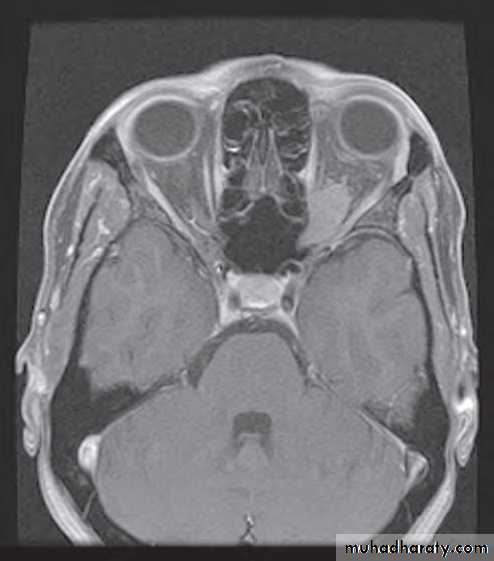

• Investigation: MRI effectively demonstrates the tumour, and may show intracranial extension if present.

• Investigation: MRI is the investigation of choice, CT shows thickening and calcification of the optic nerve.